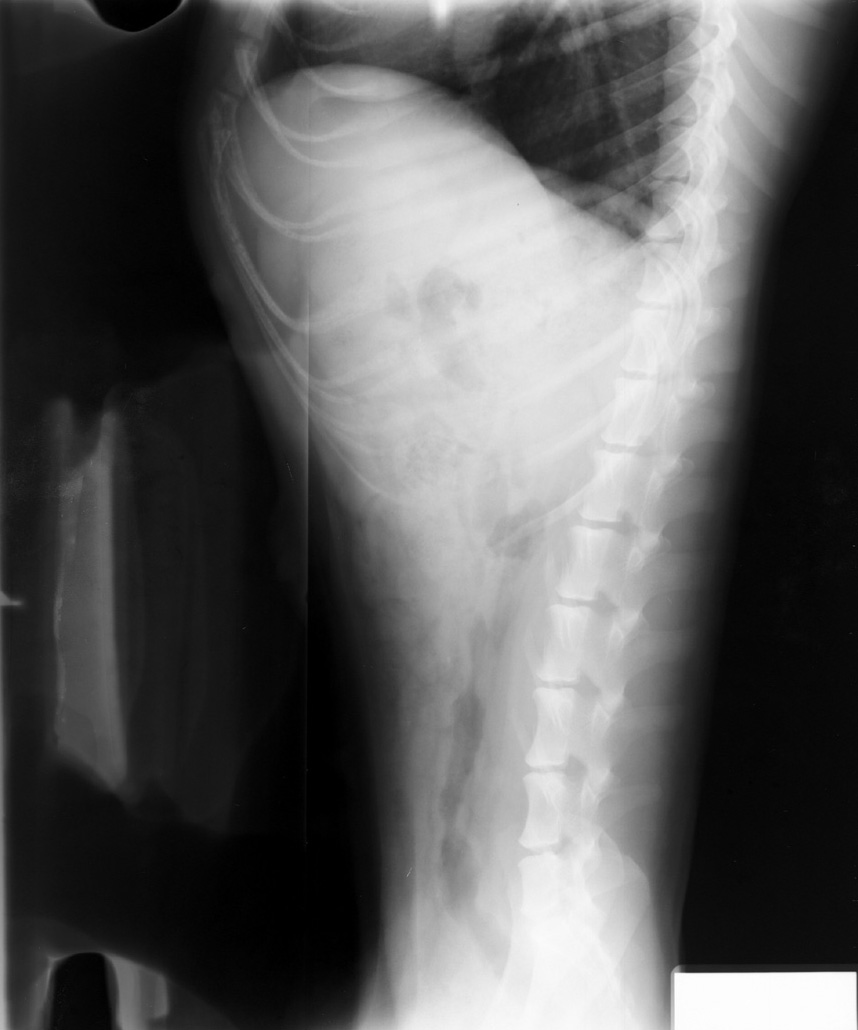

Overlapping of Film, Automatic Processing

Overlapping of two films in automatic processor. Note artifact along one long edge of each film.